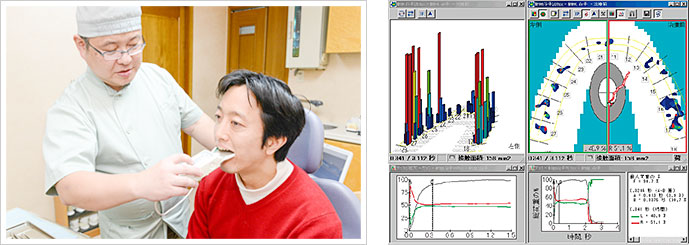

咬み合わせ位置・力・時間を分析 -「Tスキャン」

本来は感覚的にしか表現できなかった咬み合わせを、Tスキャンにより視覚的に(目で見て分かるように)解析・評価することが出来るようになりました。「咬み合わせ位置・力・時間」を分析することで、咬み合わせの力が一部の歯に偏っていないかなど、現状抱えているトラブルの発見にも繋がります。